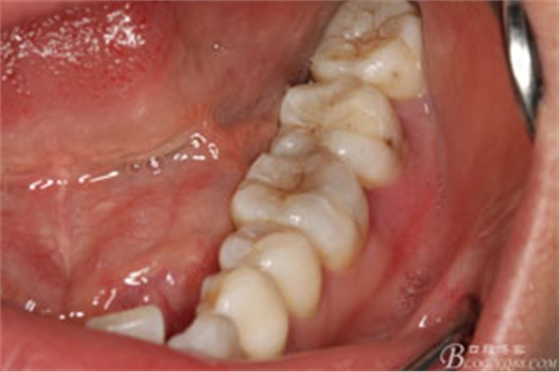

圖2.37牙冠基本完好,松動(dòng)Ⅰ度。合面有一開(kāi)髓孔被棉球覆蓋,頰側(cè)牙齦輕度紅腫。